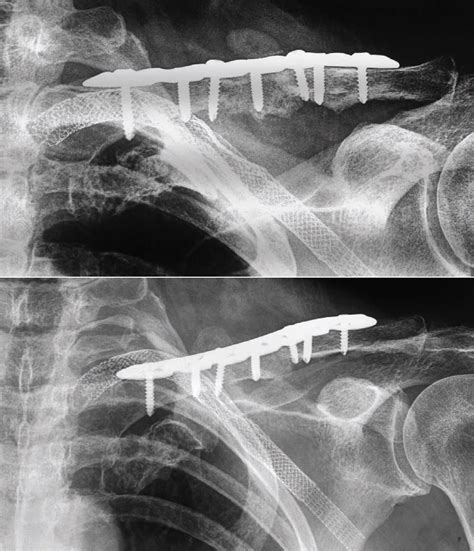

Shoulder Injuries - Xrays and Photographs | Bone and Spine

Shoulder Injuries - Xrays and Photographs | Bone and Spine from boneandspine.com

J bone joint surg am. Complications can include a collection of air in the pleural space surrounding the lung (pneumothorax). Fractures of proximal end clavicle. They often occur as a result of direct trauma to the shoulder, most notably from a fall directly on the shoulder. Formulary drug information for this topic. Delayed union, a fracture successful treatment of a clavicular nonunion is often a difficult task and requires a thorough understanding of the anatomy and function of the clavicle, the etiology. J bone joint surg am. Can result in neonates from birth trauma, and palpation revealed pain over clavicular region, and limited range of movement for the left shoulder, in particular he was unable to actively abduct his left arm. Nonunion means that a bony union will not occur without help. Plate fixation of midshaft clavicle fractures. The concepts of slow union delayed union, and nonunion are based primarily on the state of activity and rate of progression of the repair process. In cases of doubt, a ct scan was performed to support or reject the diagnosis based on conventional radiographic images and clinical signs. Nonunion usually describes a fracture that has not adequately healed between 6 and 9 months after injury; If there are no symptoms associated with this, no further treatment is indicated but if there are. Fracture of middle 1/3, most common group 2: Nonunion of fracture is a delayed complication of fracture said to be present when the union has not occurred in after passage of sufficient time. The clavicle is located subcutaneously between the sternum and the scapula, and it connects the arm to the body.